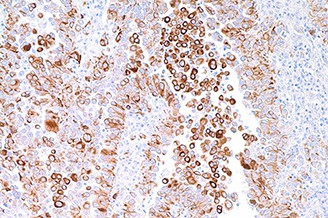

Human normal small bowel immunohistochemistry staining of CD103. Note membrane and cytoplasmic staining of Intraepithelial T lymphocytes. CD103: clone EP206

CD103, also known as alpha E integrin & human mucosal lymphocyte antigen 1, is an integrin protein with expression on intraepithelial T cells & some peripheral regulatory T cells. CD103 is expressed at high levels on tumour-infiltrating FOXP3-positive regulatory T cells in cancer and CD103-positive T cells are strongly associated with patient survival in high-grade serous ovarian cancer.

CD103 expression has been suggested as a definitive marker of intraepithelial, tumour-specific infiltrating lymphocytes. In addition, CD103-positive cells have also been identified in a small proportion of breast cancers.